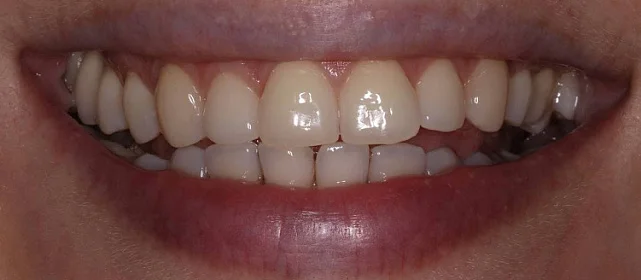

Зубы выровнены, скученность устранена. Установлены несъёмные ретейнеры на обе челюсти, сняты сканы для ретенционных кап. Ортопедия не требуется, рекомендовано лечение у терапевта.

Решение: Установили брекеты на обе челюсти. Расширили дуги, убрали скученность — всё за 15 месяцев. Визиты раз в 4–6 недель для замены дуг. После снятия зафиксировали ретейнеры на обе челюсти, сняли сканы для кап. Ортопед подтвердил, что протезирование не требуется. Терапевт рекомендовал лечение — пациентка записана.

Пятнадцать месяцев!! Я морально готовилась к двум годам минимум, начиталась всякого в интернете. Виктория Юрьевна на первой консультации сказала, что случай не самый сложный и должны уложиться побыстрее. Так и вышло. Из неприятного — первая неделя после установки и пара дней после каждой замены дуги. В остальном нормально, привыкла быстро. Когда сняли и я увидела зубы — не поверила, что это мои. Теперь вот к терапевту надо сходить, подлечить пару зубов, и вообще всё.